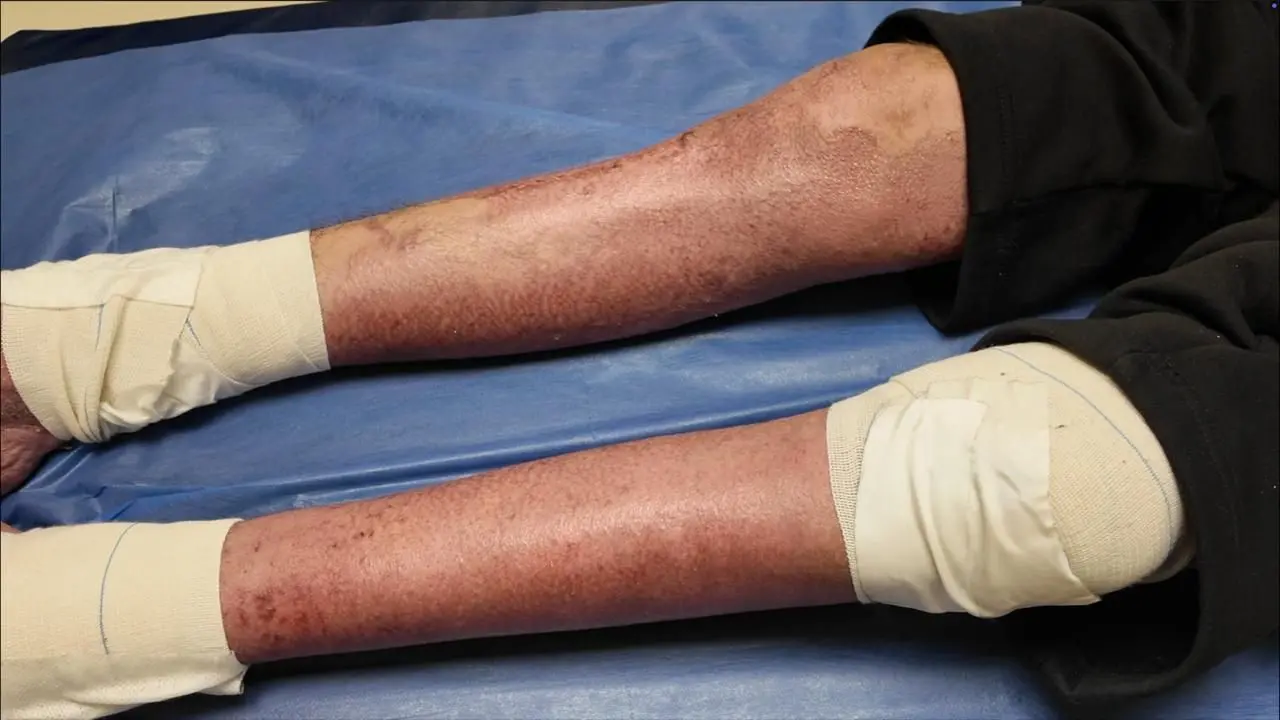

أصيب إبراهيم بحروق شديدة بلغت 75 في المئة، وكادت تودي بحياته لولا التدخل الطبي السريع وزراعة الجلد البشري المستورد.

على مدار نحو شهرين، بدأت نسبة الحروق تنخفض تدريجيًا من 75% إلى 63% ثم 41%، وعندها قرر الفريق الطبي إجراء عملية زراعة الجلد. أوضح الأطباء أن الجلد سيكون "مؤقتًا ومستوردًا من الخارج" ليسمح للأنسجة بالالتئام بسرعة أكبر.

وسرعان ما انخفضت نسبة الحروق إلى 14%، ثم خرج إبراهيم من المستشفى بنسبة لا تتجاوز 5%، وهو لا يزال يتلقى المتابعة والعلاج الطبيعي بشكل دوري.

تشير السويدي إلى أن الحروق التي تتجاوز 30–40%، خصوصًا لدى الأطفال، تترك مساحات كبيرة من الجلد مكشوفة، ما يزيد خطر العدوى والتسمم. والجلد المزروع يعمل كغطاء بيولوجي مؤقت حتى يبدأ الجسم ببناء أنسجته وخلاياه، ثم يقوم بطرد الجلد المزروع تلقائيًا.

ويؤكد "الدكتور أيمن معتوق"، استشاري جراحة التجميل والحروق، أن نسبة الوفاة عالية جدًا إذا تجاوزت الحروق 50%، وقد تصل إلى 100% لدى الأطفال وكبار السن أو المصابين بأمراض مزمنة. تغطية الجلد المتبرع به يحمي المريض ويحول الجسم من حالة هدم إلى حالة بناء، ويتيح إمكانية إجراء عمليات ترقيع لاحقًا.